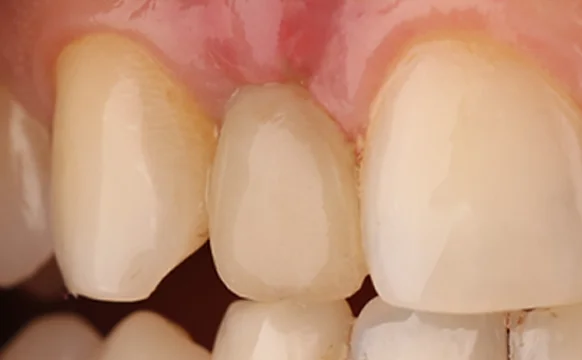

Имплантация передних зубов

Восстановление передних зубных единиц — сложная процедура, позволяющая восстановить природную красоту и здоровье улыбки.

Реставрация передних зубов

Процедура реставрации зубов направлена на восстановление их эстетики и функциональных возможностей после травм или стоматологических заболеваний.